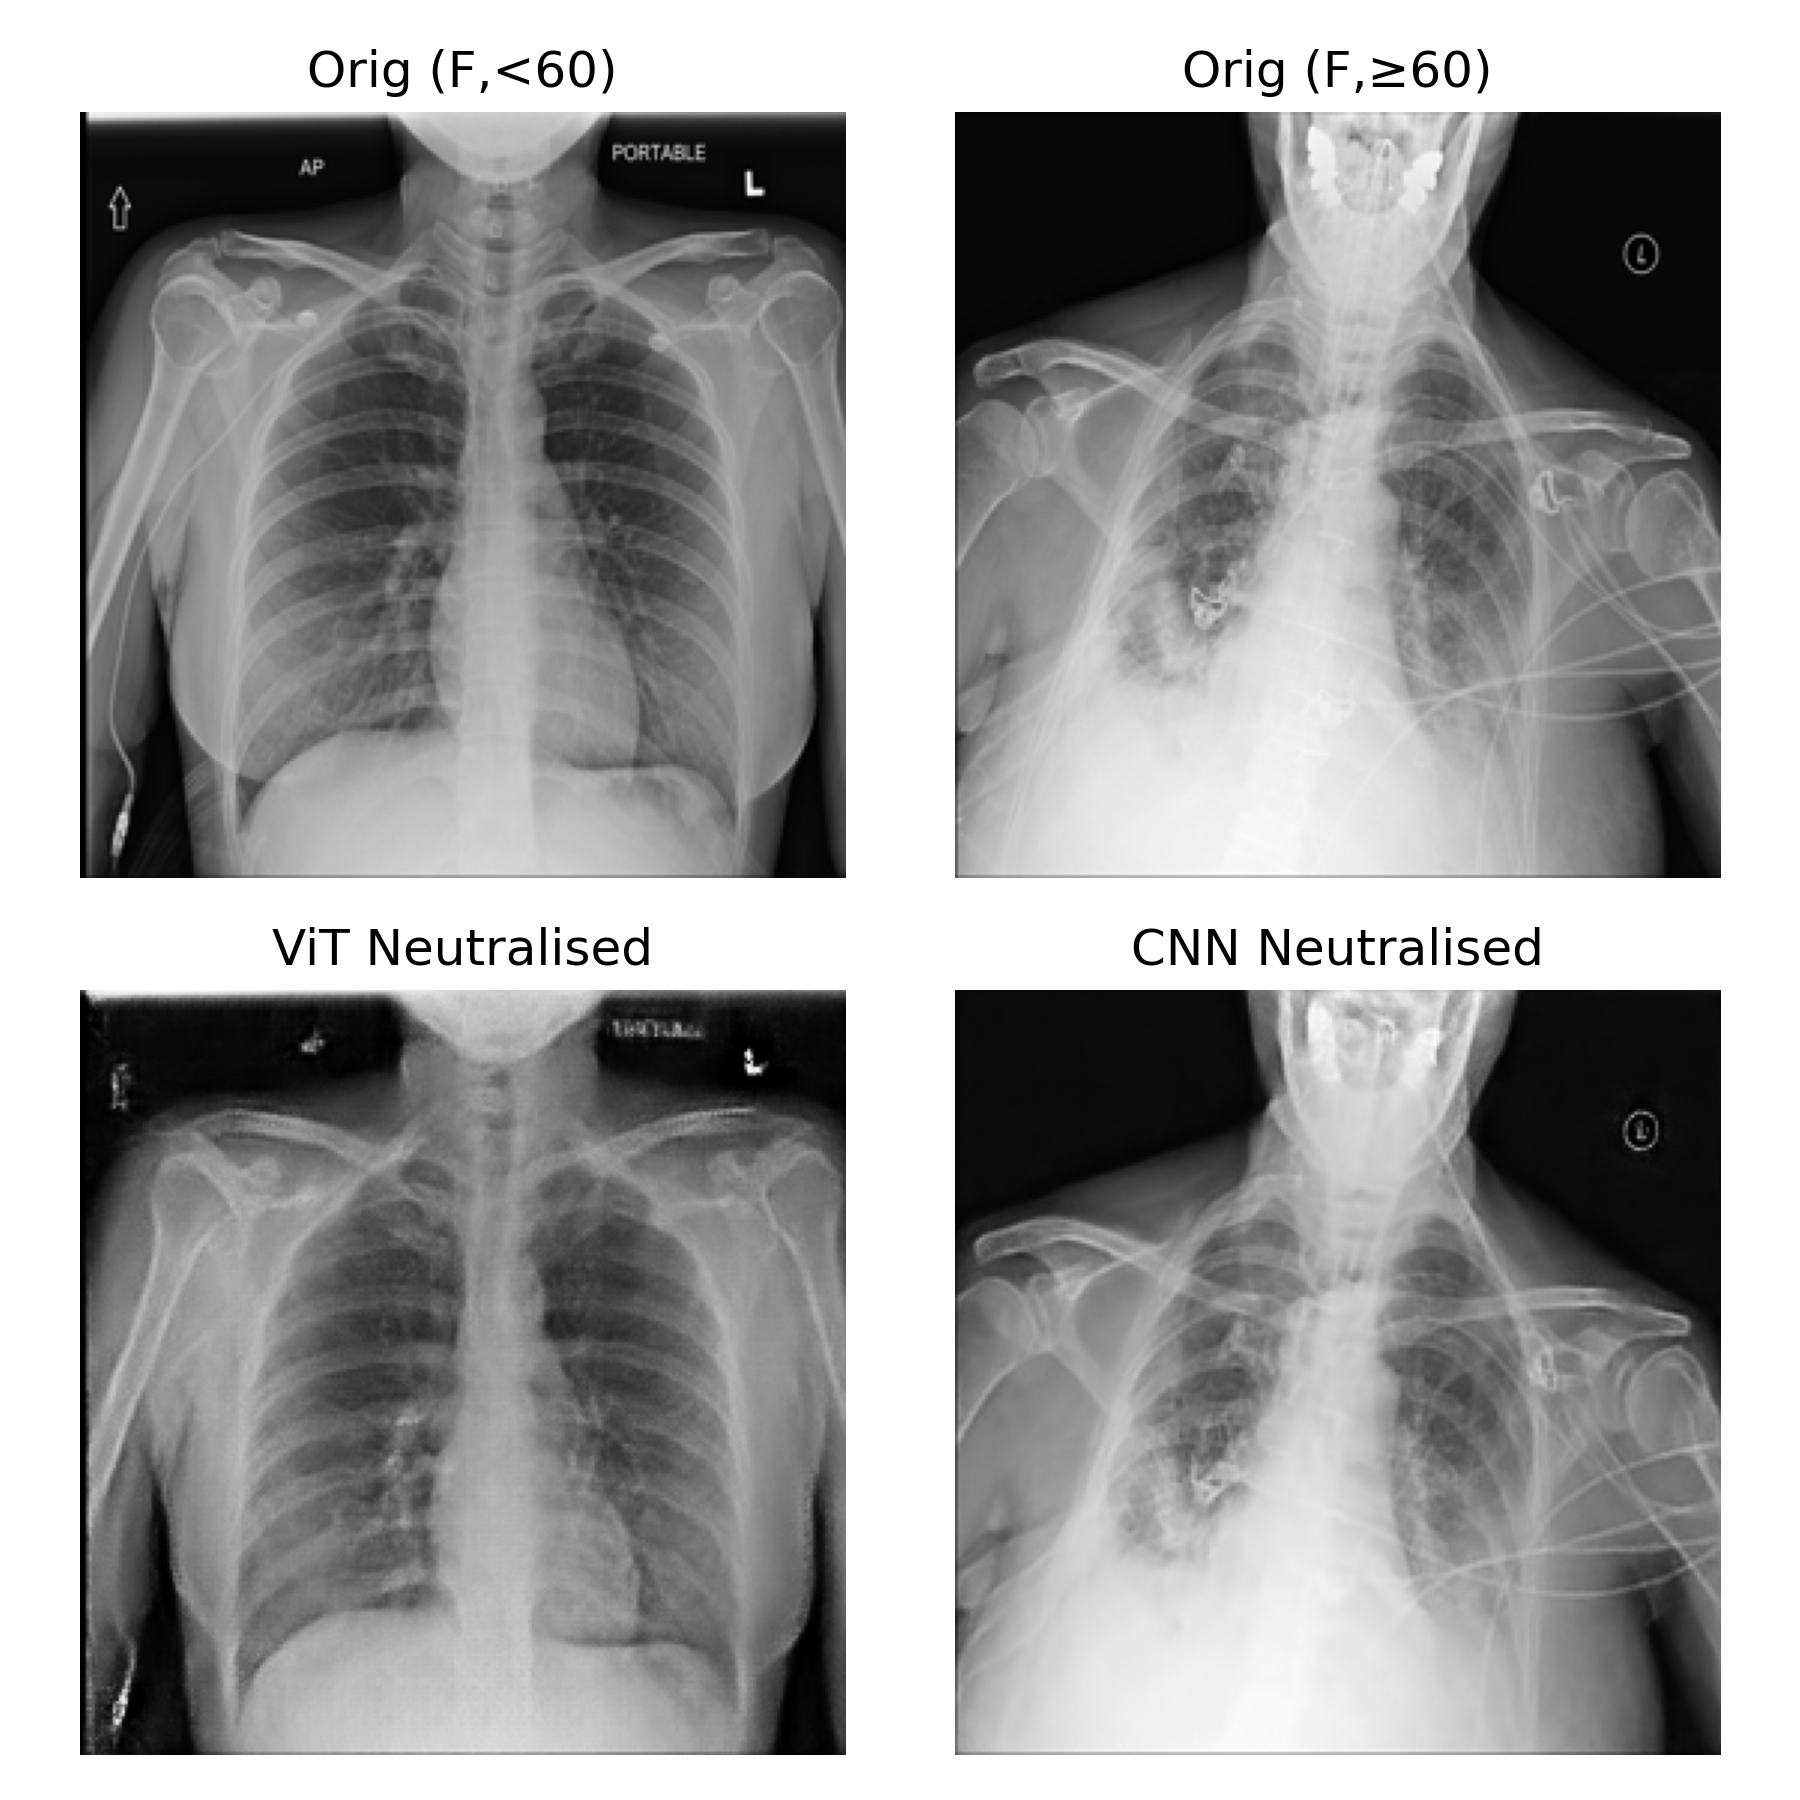

4.3.4 Illustrative examples of attribute-neutralization

Two qualitative views highlight how the neutralizers behave on individual images. Appendix Figures 36 and 37 show per-patient AI-judge and diagnosis outputs before and after neutralization, contrasting the CNN- and ViT-based pipelines. For each patient, the original CXR is displayed alongside its neutralized counterpart at , together with AI-judge outputs (Age, Sex) and the five most likely findings predicted by the Disease Diagnosis Model. Qualitatively, the CNN neutralizer suppresses attributes inconsistently and distorts diagnosis scores, whereas the ViT neutralizer achieves stronger attribute removal with minimal diagnostic drift.

Figure 17 zooms in on two example images (female y and female y) to visualise the edits themselves: ViT makes subtle changes around attribute-informative regions (breast tissue), whereas the CNN-based neutralizer leaves the image almost unchanged.